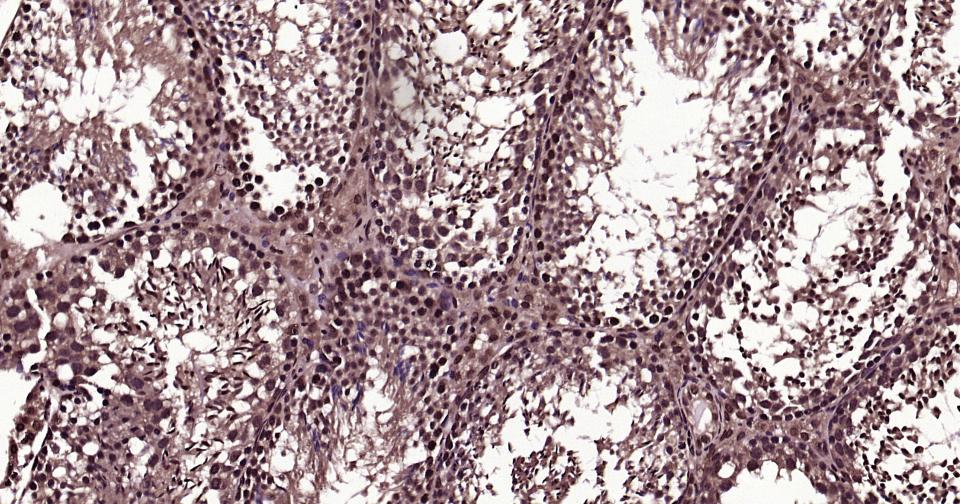

Paraformaldehyde-fixed, paraffin embedded Human Prostate Tumor; Antigen retrieval by boiling in sodium citrate buffer (pH6.0) for 15 min; Antibody incubation with K27-linkage specific ubiquitin Monoclonal Antibody, Unconjugated(bsm-63007R) at 1:200 overnight at 4°C, followed by conjugation to the bs-0295G-HRP and DAB (C-0010) staining and DAB (C-0010) staining.